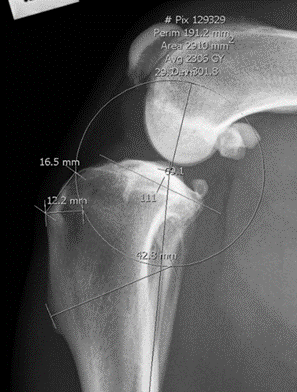

Determining Saw Blade Radius